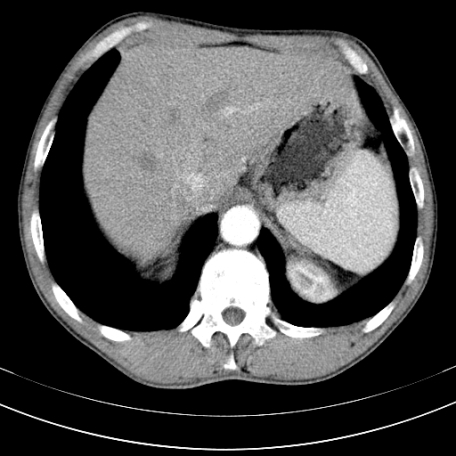

标题: CT21441:男55岁,上腹部胀痛半年余,请老师们看看是后腹膜淋巴 [打印本页]

标题: CT21441:男55岁,上腹部胀痛半年余,请老师们看看是后腹膜淋巴

眼拙!仅见胰腺稍丰满,脾大。

转移瘤或淋巴瘤